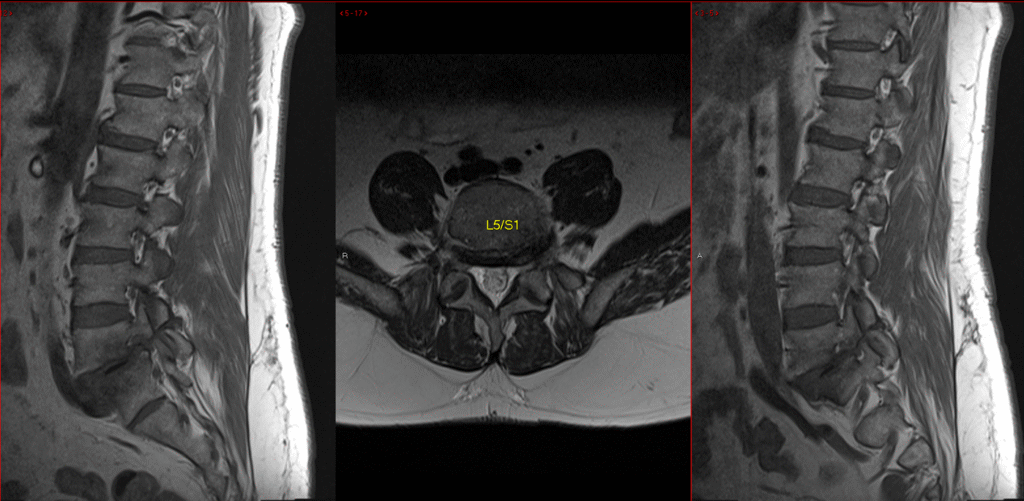

Transforaminal Lumbar Spine Fusion